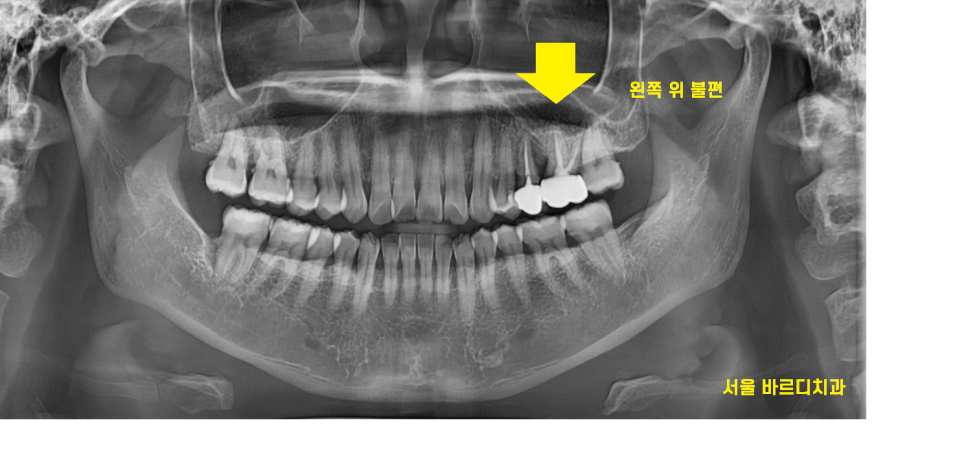

22.12.09

왼쪽 위쪽이 통증이 느껴진다고

심각한거 같아요 원장님 ㅠㅠ

덕풍동 치과를 방문해주셨어요~

예전에 치료했던 치아가 문제가 생겼는데

이런...

치아가 부러지기 직전이에요ㅠㅠ

뿌리 부분도 노출되어있고

금이 많이간 모습입니다.